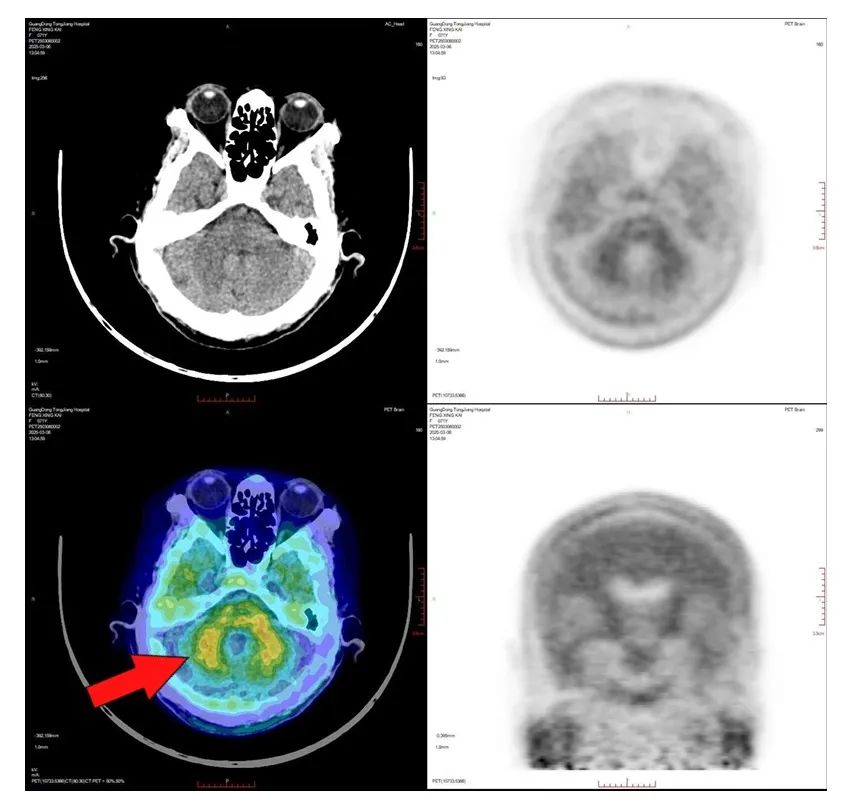

2025年3月4日,国内首款Aβ-PET显像剂获得批文,使得β-淀粉样蛋白正电子发射断层扫描技术早期诊断AD成为现实。该技术可以“锁定”患者脑内的致病蛋白沉积,可以在症状出现前10-15年前精准诊断AD,还可用于靶向治疗的疗效监测,解决了早发现早治疗AD的关键性难题。

2025年3月4日,ky获批β-淀粉样蛋白正电子发射断层扫描技术。3月6日早上,临床诊断为阿尔茨海默病的冯阿姨,成为佛山首批接受该项检查的患者。周思朗副院长、核医学科周世辉主任、神经内科董晓莉主任、老年科丘伟贤主任和设备技术专家一起,顺利完成了β-淀粉样蛋白正电子发射断层扫描。ky还安排了高质量的远程会诊,让首批病例的报告质量达到了行业的高水平。

Aβ-PET检查,患者仅需静脉注射微量放射性显像剂,等待90分钟后,20分钟可完成全身扫描。该技术高效无创,通过图像量化脑内淀粉样斑块的分布与浓度,进行精准诊断和病情评估。